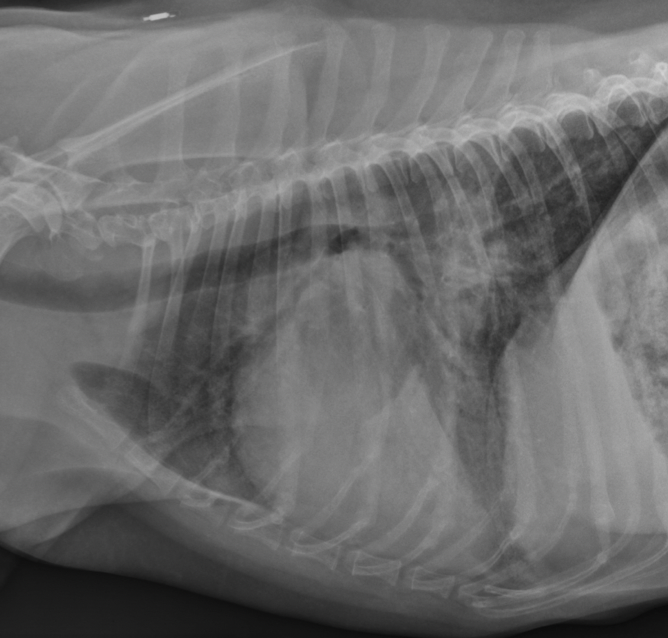

xray of dogs with MVD will show

A

big heart

LA,LV enlargement

pulmonary venous distension

perihilar interstital/alveolar (CHF/edema)